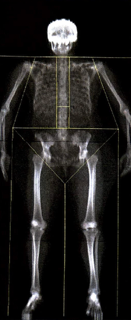

At 51 years old, after years of teaching and practicing Original Hot Yoga and Inferno Hot Pilates, I decided to check in on my bone health with a DEXA scan — a test that measures bone density. I wanted to know how my body — and especially my bones — had responded to years of heat, breath, and movement.

To my surprise and delight, my DEXA scan showed me I have stronger bones than most 20-30 year olds — what? And I almost exclusively do OG Hot Yoga and Inferno Hot Pilates, sprinkled with outdoor activity.

Here’s my results:

📊 Bone Mineral Density (BMD): 1.216 g/cm²

📈 T-score: +1.5

📈 Z-score: +1.4

For context, a T-score above −1.0 is considered normal.

A positive score means my bones are actually denser and stronger than average — even compared to younger women.